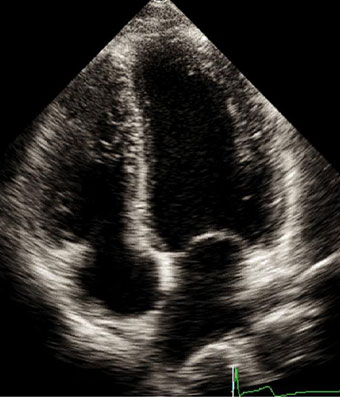

Ecocardiografía

El ecocardiograma o ecocardiografía utiliza ondas sonoras de alta frecuencia para obtener imágenes del corazón en vivo y que son proyectadas en una pantalla. Este auxiliar diagnóstico aporta información en 30 a 60 minutos de la forma, tamaño, función y movimiento del corazón así como de sus estructuras internas, como por ejemplo las válvulas cardiacas. Este estudio es seguro en pacientes adultos, en pacientes pediátricos (ecocardiograma pediátrico) o incluso en mujeres embazadas para estudiar el desarrollo del corazón del bebé en la cavidad uterina (ecocardiografía fetal).

Las imágenes ecocardiografías del corazón pueden ser obtenidas en diferentes modos (unidimensional, bidimensional o tridimensional, Doppler, Doppler color), utilizando una sonda externa (ecocardiograma transtorácico) o una sonda interna (ecocardiograma transesofágico) y puede ser adquirido en reposo, en estrés con esfuerzo físico o con el uso de medicamentos (estrés con dobutamina), dependiendo del diagnóstico y de la indicación de tú médico.